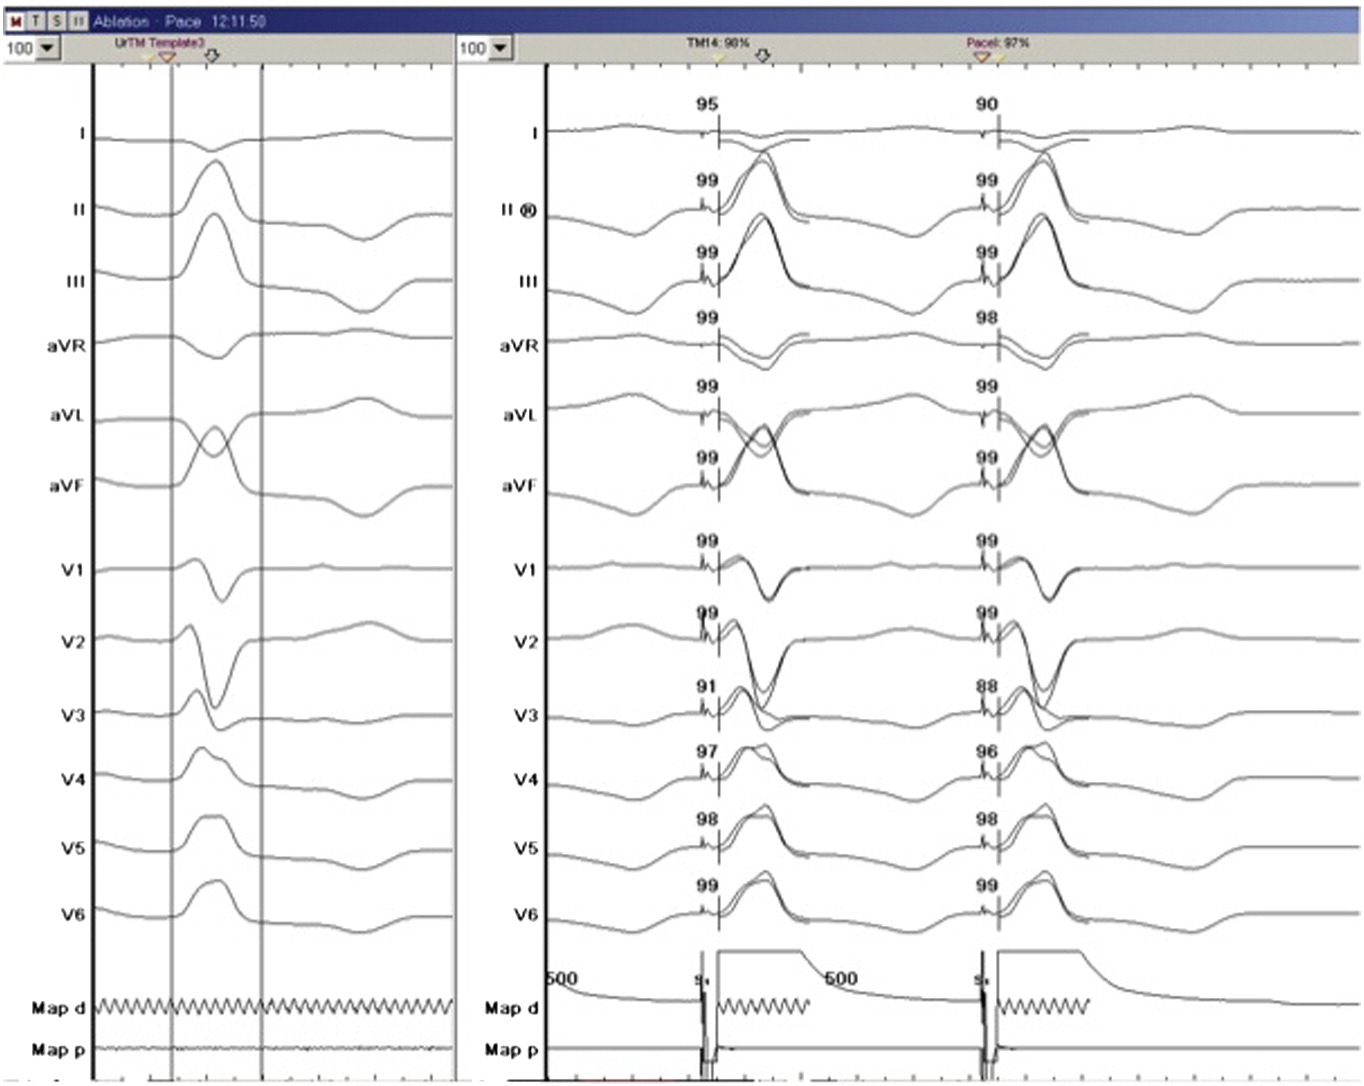

Automated matching

success_match.jpg

Jakob Lüker et al. Automated template matching correlates with earliest activation during mapping of idiopathic premature ventricular contractions. IJC Heart & Vessels Volume 4 2014 Pages 25-29